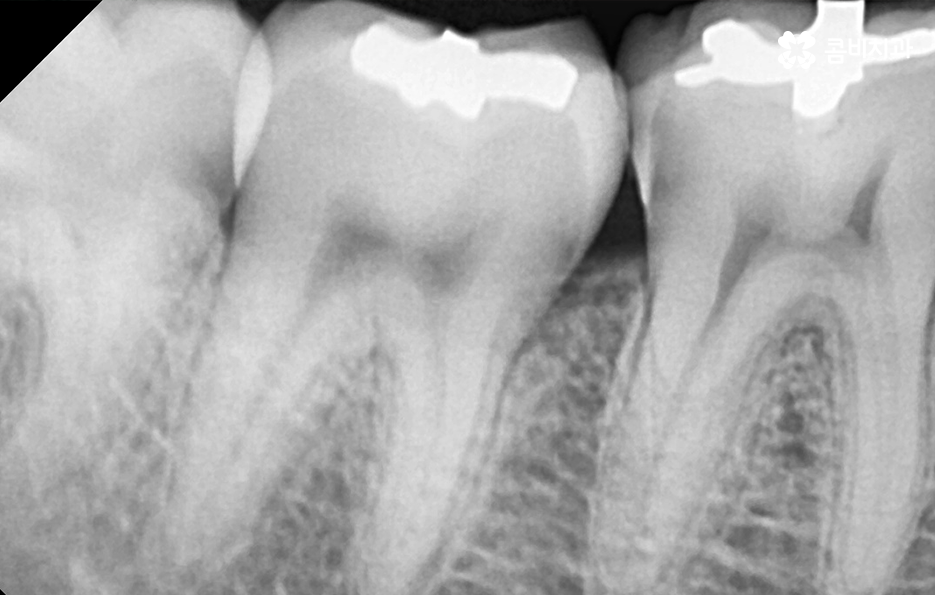

오늘은 자연치아를 결국 잃게 되면 대표적인 사례 중에서 오래된 보철물 혹은 보철물 관리가 잘 안되어 결국 발치로 이어지는 사례에 대해서 알아볼 거예요. 오래된 보철물 속에서 진행되는 2차 충치는 알아차리기도 쉽지 않고 이미 깊어지면 치아 뿌리 쪽으로 충치가 진행되어 발치로 이어지는 경우가 많다는 점에서 보철물 관리의 중요성에 대해서 재인식하는 포스팅이 되길 바라고 있어요

보통 어금니 크라운을 씌운 경우에는 신경치료를 한 후에 크라운을 씌운 경우가 많기 때문에 이미 크라운 속에 충치가 심하게 진행되어도 통증과 같은 증상으로 문제를 잘 못느끼는 경우가 많이 있는데요

치아 문제에 대해서 안아프면 별 문제 없겠지 하고 잘 지내고 있다가 예전에 씌워서 기억도 잘 안나는 크라운이 흔들리거나 냄새, 잇몸 염증 등이 발생하여 치과를 찾게 되었는데 이미 심각한 수준으로 치아 내부에 충치가 진행되어 결국 발치에 이르게 되는 경우가 많이 있어요

크라운 혹은 오래된 보철물 내부에 2차 충치가 발생된 경우에 자연치아를 보존할 수 있는지에 대한 판단은 엑스레이 만으로 진단할 수 있는 문제는 아니며 치아 내부에 충치가 어느정도나 진행되었고 잔존하는 치아의 양이 어느정도나 되는지에 따라서 발치 혹은 치아 보존 치료에 대한 판단을 할 수 있어요

이미 신경치료를 했던 치아라고 해도 보철물 제거 후에 충치를 잘 치료하고 재신경치료를 통해서 치아를 보존할 수 있는 경우가 있고 발치 후 임플란트를 해야하는 경우도 있는데요

이러한 판단 기준은 치아 내부에서 충치가 발생되었을 때 충치가 얼마나 치아 뿌리 쪽으로 깊어졌는지 혹은 살릴 수 있는 치아가 얼마나 잔존하는지에 따라서 다르며 치과의사 역시도 치아 속을 확인해보고 충치를 제거해봐야 알기 때문에 치과의사의 숙련도, 경험도 중요하겠지만 치과의 내원 시점이 무척이나 중요하기 때문에 보철물이 오래된 경우에는 꼭 주기적으로 치과 검진을 하시고 의사의 소견 하에 크라운의 교체가 필요하다면 문제가 커지기 전에 재치료를 적절히 받는 것이 자연치아 보존에 중요할 거예요